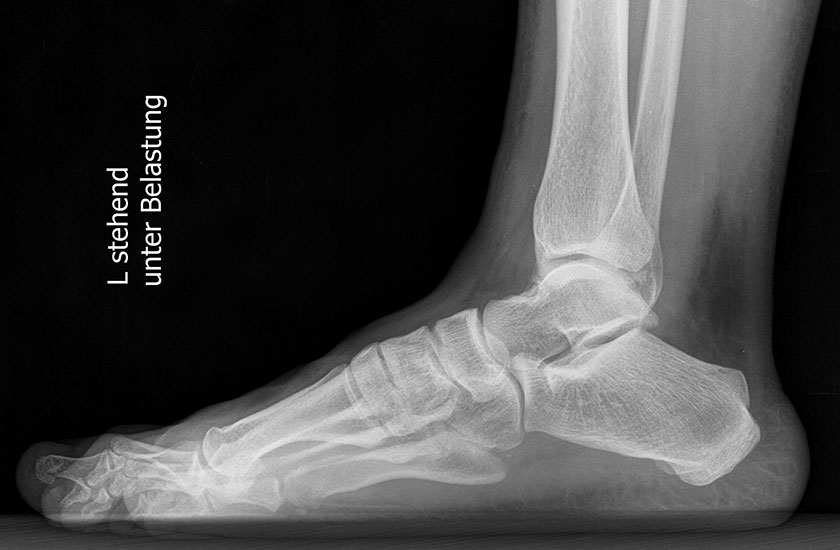

Standard ist die belastete Röntgenaufnahme des Fußes dorso-plantar und seitlich. Günstig ist eine Röhrenkippung von 10°-20°, um die Gelenke der Lisfranc-Linie einsehen zu können.

Ergänzend kann eine Schrägaufnahme hilfreich sein. Bei Metatarsalgien oder Pathologien der Sesambeine liefert die Sprinteraufnahme zusätzliche Informationen. Bei einer Pes planovalgus Fehlstellung wird ergänzend ein Saltzman view durchgeführt.

• Elevation/ Plantarisierung I. Strahl

• Pes metatarsus adductus